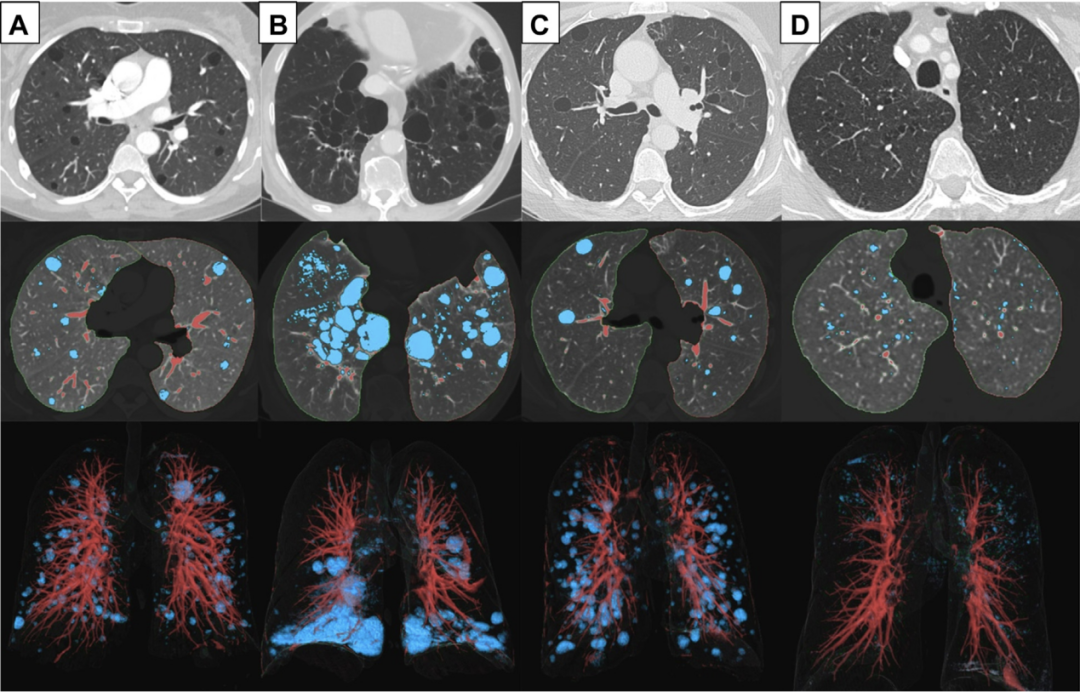

图1 A-D,弥漫性囊性肺疾病的囊肿分布

胸部CT成像显示了囊性病变(蓝色)在 (A)淋巴管平滑肌瘤病(LAM)、(B)Birt-Hogg-Dubé综合征(BHD)、(C)淋巴细胞性间质性肺炎(LIP)和(D)肺朗格汉斯细胞组织细胞增生症(PLCH)中的分布。注意LAM中的囊性病变均匀分布;BHD中椭圆形囊肿以胸膜下、下叶为主;LIP中的沿血管周围的囊肿;以及PLCH中以上肺叶为主的囊肿。